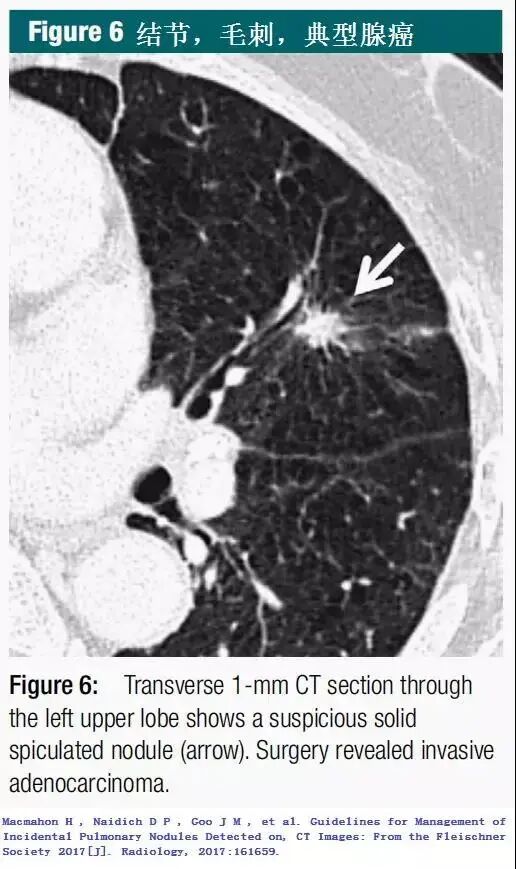

胸部CT在体检中的应用越来越普遍,很多人在做完CT后被告知:肺上长了结节。 其实体检被检测出的肺结节只有5%是恶性的。 我们一直在跟大家强调肺结节问题,尽管这样还是有很多患者不放心,担心的睡不着觉。 那什么样的肺结节该切?什么样的不该切呢? 有一点要明确肺结节不等于肺癌,它在人体内出现的原因大致分为三种:炎性疾病、先天性疾病和肿瘤。 它并不是一个具体的疾病名称,它跟咳嗽一样是一种表现,感冒发烧会咳嗽,肺炎了也会咳嗽。肺结节就是指在影像检查上看到的直径≤3cm、类圆形的、密度增高的实质性或亚实质性的肺部阴影。 首先给大家看看哪些是良性的(来自Fleischner协会指南的经典CT) CT影像判断肺结节的良恶性主要是从结节大小、形态、密度等特征来进行判断(注意:临床上具体需由专业医生综合分析判断,切勿自行臆断)。 1.结节大小:随着肺结节体积增大,其恶性概率也随之增加。但肺结节大小的变化对其定性诊断价值有限,还需密切结合形态及密度的改变; 2.结节外形:良性肺结节边缘清晰、光滑;恶性肺结节有分叶、空泡、毛刺、血管聚集、胸膜凹陷的特点; 3.结节密度:部分实性结节的恶性概率最高,其次是磨玻璃结节和实性结节。 CT图是诊断的第一步,要诊断结节情况需要结合其他相关检查,如结核菌素试验是否阳性,肿瘤标志物情况等。具体检查需要做哪些?不要慌,找专科医生并信任他。